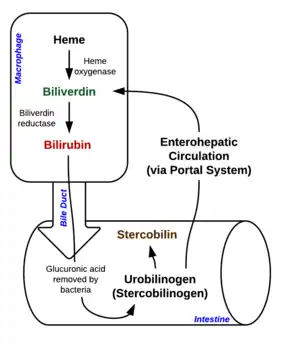

Normal heme metabolism

Prehepatic metabolism

When red blood cells complete their lifespan of about 120 days, or if they are damaged, they rupture as they pass through the reticuloendothelial system, and cell contents including hemoglobin are released into circulation. Macrophages phagocytose free hemoglobin and split it into heme and globin. Two reactions then take place with the heme molecule. The first oxidation reaction is catalyzed by the microsomal enzyme heme oxygenase and results in biliverdin (green color pigment), iron, and carbon monoxide. The next step is the reduction of biliverdin to a yellow color tetrapyrrole pigment called bilirubin by cytosolic enzyme biliverdin reductase. This bilirubin is "unconjugated", "free", or "indirect" bilirubin. Around 4 mg of bilirubin per kg of blood are produced each day.[32] The majority of this bilirubin comes from the breakdown of heme from expired red blood cells in the process just described. Roughly 20% comes from other heme sources, however, including ineffective erythropoiesis, and the breakdown of other heme-containing proteins, such as muscle myoglobin and cytochromes.[32] The unconjugated bilirubin then travels to the liver through the bloodstream. Because this bilirubin is not soluble, it is transported through the blood bound to serum albumin.

Hepatic metabolism

Once unconjugated bilirubin arrives in the liver, liver enzyme UDP-glucuronyl transferase conjugates bilirubin + glucuronic acid → bilirubin diglucuronide (conjugated bilirubin). Bilirubin that has been conjugated by the liver is water-soluble and excreted into the gallbladder.

Posthepatic metabolism

Bilirubin enters the intestinal tract via bile. In the intestinal tract, bilirubin is converted into urobilinogen by symbiotic intestinal bacteria. Most urobilinogen is converted into stercobilinogen and further oxidized into stercobilin. Stercobilin is excreted via feces, giving stool its characteristic brown coloration.[33] A small portion of urobilinogen is reabsorbed back into the gastrointestinal cells. Most reabsorbed urobilinogen undergoes hepatobiliary recirculation. A smaller portion of reabsorbed urobilinogen is filtered into the kidneys. In the urine, urobilinogen is converted to urobilin, which gives urine its characteristic yellow color.[33]